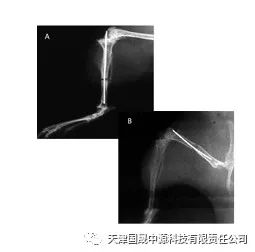

•X光拍照分析